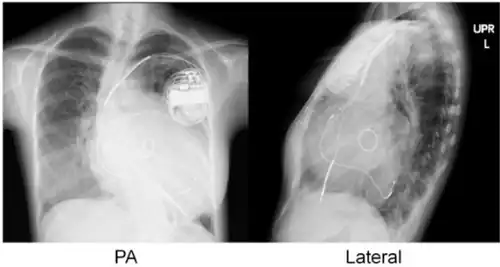

Cardiac resynchronisation therapy (CRT or CRT-P) is the insertion of electrodes in the left and right ventricles of the heart, as well as on occasion the right atrium, to treat heart failure by coordinating the function of the left and right ventricles via a pacemaker, a small device inserted into the anterior chest wall.[1]

CRT requires the placement of an electrical device for biventricular pacing, along with placement of (at least) two pacing leads, to facilitate stable left ventricular and right ventricular pacing. For all elements, the first stage of the process is local anaesthetic followed by incision to allow for approach from the appropriate vein. From here, the leads and device can be inserted.[1]

Device placement

The device is inserted in a subcutaneous pocket created by the surgeon, the choice of left or right side of the chest wall is determined mainly by the patient's preference or location of preexisting device. The device, similar to that of a traditional pacemaker, is generally no larger than a pocket watch and has inserts for the electrode leads.[1]